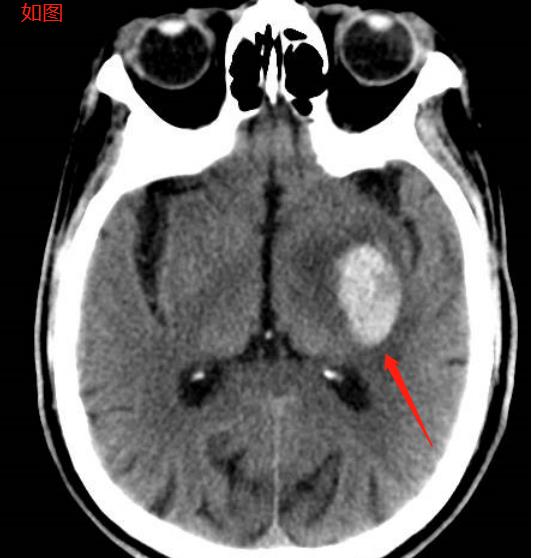

辅助检查:1.头颅CT是确诊脑出血的首选检查。CT可准确显示出血的部位、大小、脑水肿情况及是否破人脑室等,有助于指导治疗和判定预后。早期血肿在CT上表现为圆形或椭圆形的高密度影,边界清楚。(如图)